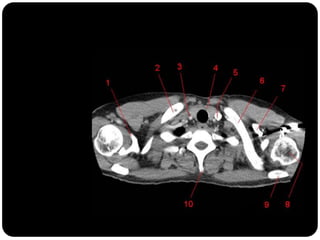

Traquéia       Pulmão direito:

Brônquios           LSD: anterior, apical e posterior;

Bronquíolos

      LM: medial e lateral;

Alvéolos

      LID: superior, basal medial, basal lateral,

basal anterior, basal posterior;

 Pulmão esquerdo:

     LSE: apicoposterior, anterior,

superior(língula), inferior(língula);

     LIE: segmento superior, basal antero-

medial, basal lateral e basal posterior;